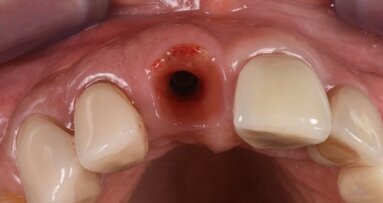

Sei mesi dopo i pazienti sono stati sottoposti ad intervento chirurgico per il posizionamento dell’impianto. Eseguita l’anestesia locale e scollati i lembi a spessore totale in mandibola, è stata eseguita una carotatura per l’analisi istologica della qualità dell’osso (Figg. 4, 5). Nello stesso sito, dopo averlo adeguatamente preparato è stato posizionato un impianto DAE 4 x 11,5 mm al livello dell’osso crestale (Fig. 6). Successivamente sono stati suturati i lembi (Seta, Ethicon 4.0, Johnson & Johnson Medical, New Brunswick/NJ, USA). Infine, prescritti un antinfiammatorio (Nimesulide 100 mg, 2 volte al giorno per 3 giorni), un analgesico (Paracetamolo 500 mg, 1 compressa ogni 8 ore per 3 giorni), e clorexidina 0.12% durante la fase post-operatoria insieme a istruzioni complete all’igene orale. La sutura è stata rimossa a 10 giorni dall’intervento chirurgico. Sei mesi dopo, l’impianto è stato protesizzato con una corona singola avvitata in metallo-ceramica. A 3 mesi e a 3 anni sono state eseguite le radiografie periapicali parallele.

La radiografia eseguita immediatamente dopo il posizionamento dell’impianto ha mostrato che gli impianti dentali erano perfettamente posizionati a livello dell’osso crestale (Fig. 6). Le analisi istologiche della carotatura di osso prelevato hanno mostrato che a 6 mesi dall’intervento di conservazione dell’alveolo, si è formato nuovo tessuto osseo vitale e sono ancora presenti granuli del biomateriale utilizzato (Fig. 12). Il follow up radiografico a 3 anni indica una situazione ossea invariata con l’impianto ancora a livello dell’osso crestale. La parte protesica ancora in buone condizioni senza segni d’infiammazione, né si sono riscontrate mucositi o perimplantiti. I restauri privi di complicanze tecniche.